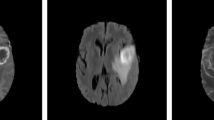

Magnetic resonance imaging (MRI) is the most clinically used and gifted modality to identify brain abnormalities in individuals who might be at risk for brain cancer. To date, automated brain tumor segmentation from MRI modalities remains a sensitive, computationally expensive, and a demanding task. This paper presents an automated and robust segmentation method to enable investigators to make successful diagnosis and planning of radiosurgery by reducing the risk factor and study duration. The proposed system consists of following steps: (1) remove the non-brain part from MRI, (2) estimate saliency map of MRI, (3) use the salient region (tumor) as an identification marker and segment the salient object by finding the “optimal” closed contour around the tumor. The system has been tested on real patient images with excellent results. The qualitative and quantitative evaluations by comparing with ground truths and with other existing approaches demonstrate the effectiveness of the proposed method.